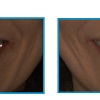

術前と術後の口元の比較です。